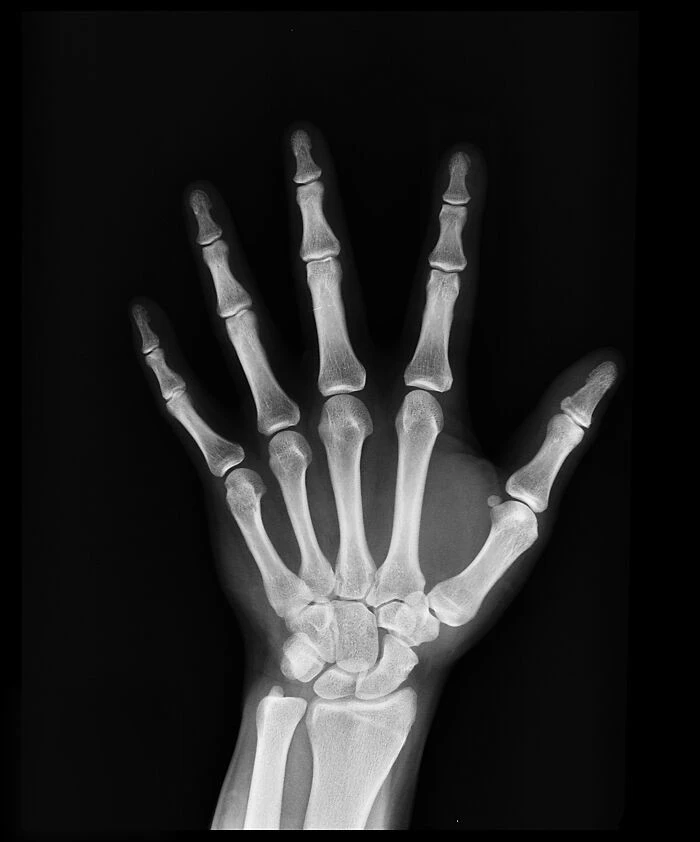

14. «В пальцах рук и ног нет мышц. Все мышцы, которые контролируют их через сухожилия, находятся в предплечьях/кистях и голенях/ступнях. Твои пальцы как марионетки на ниточках. Сладких снов»